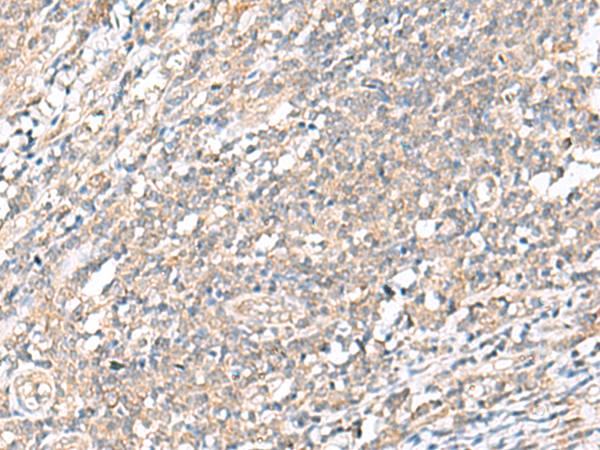

分类: 科研抗体货号: P09962别名:应用: IHC反应种属: Human, Mouse